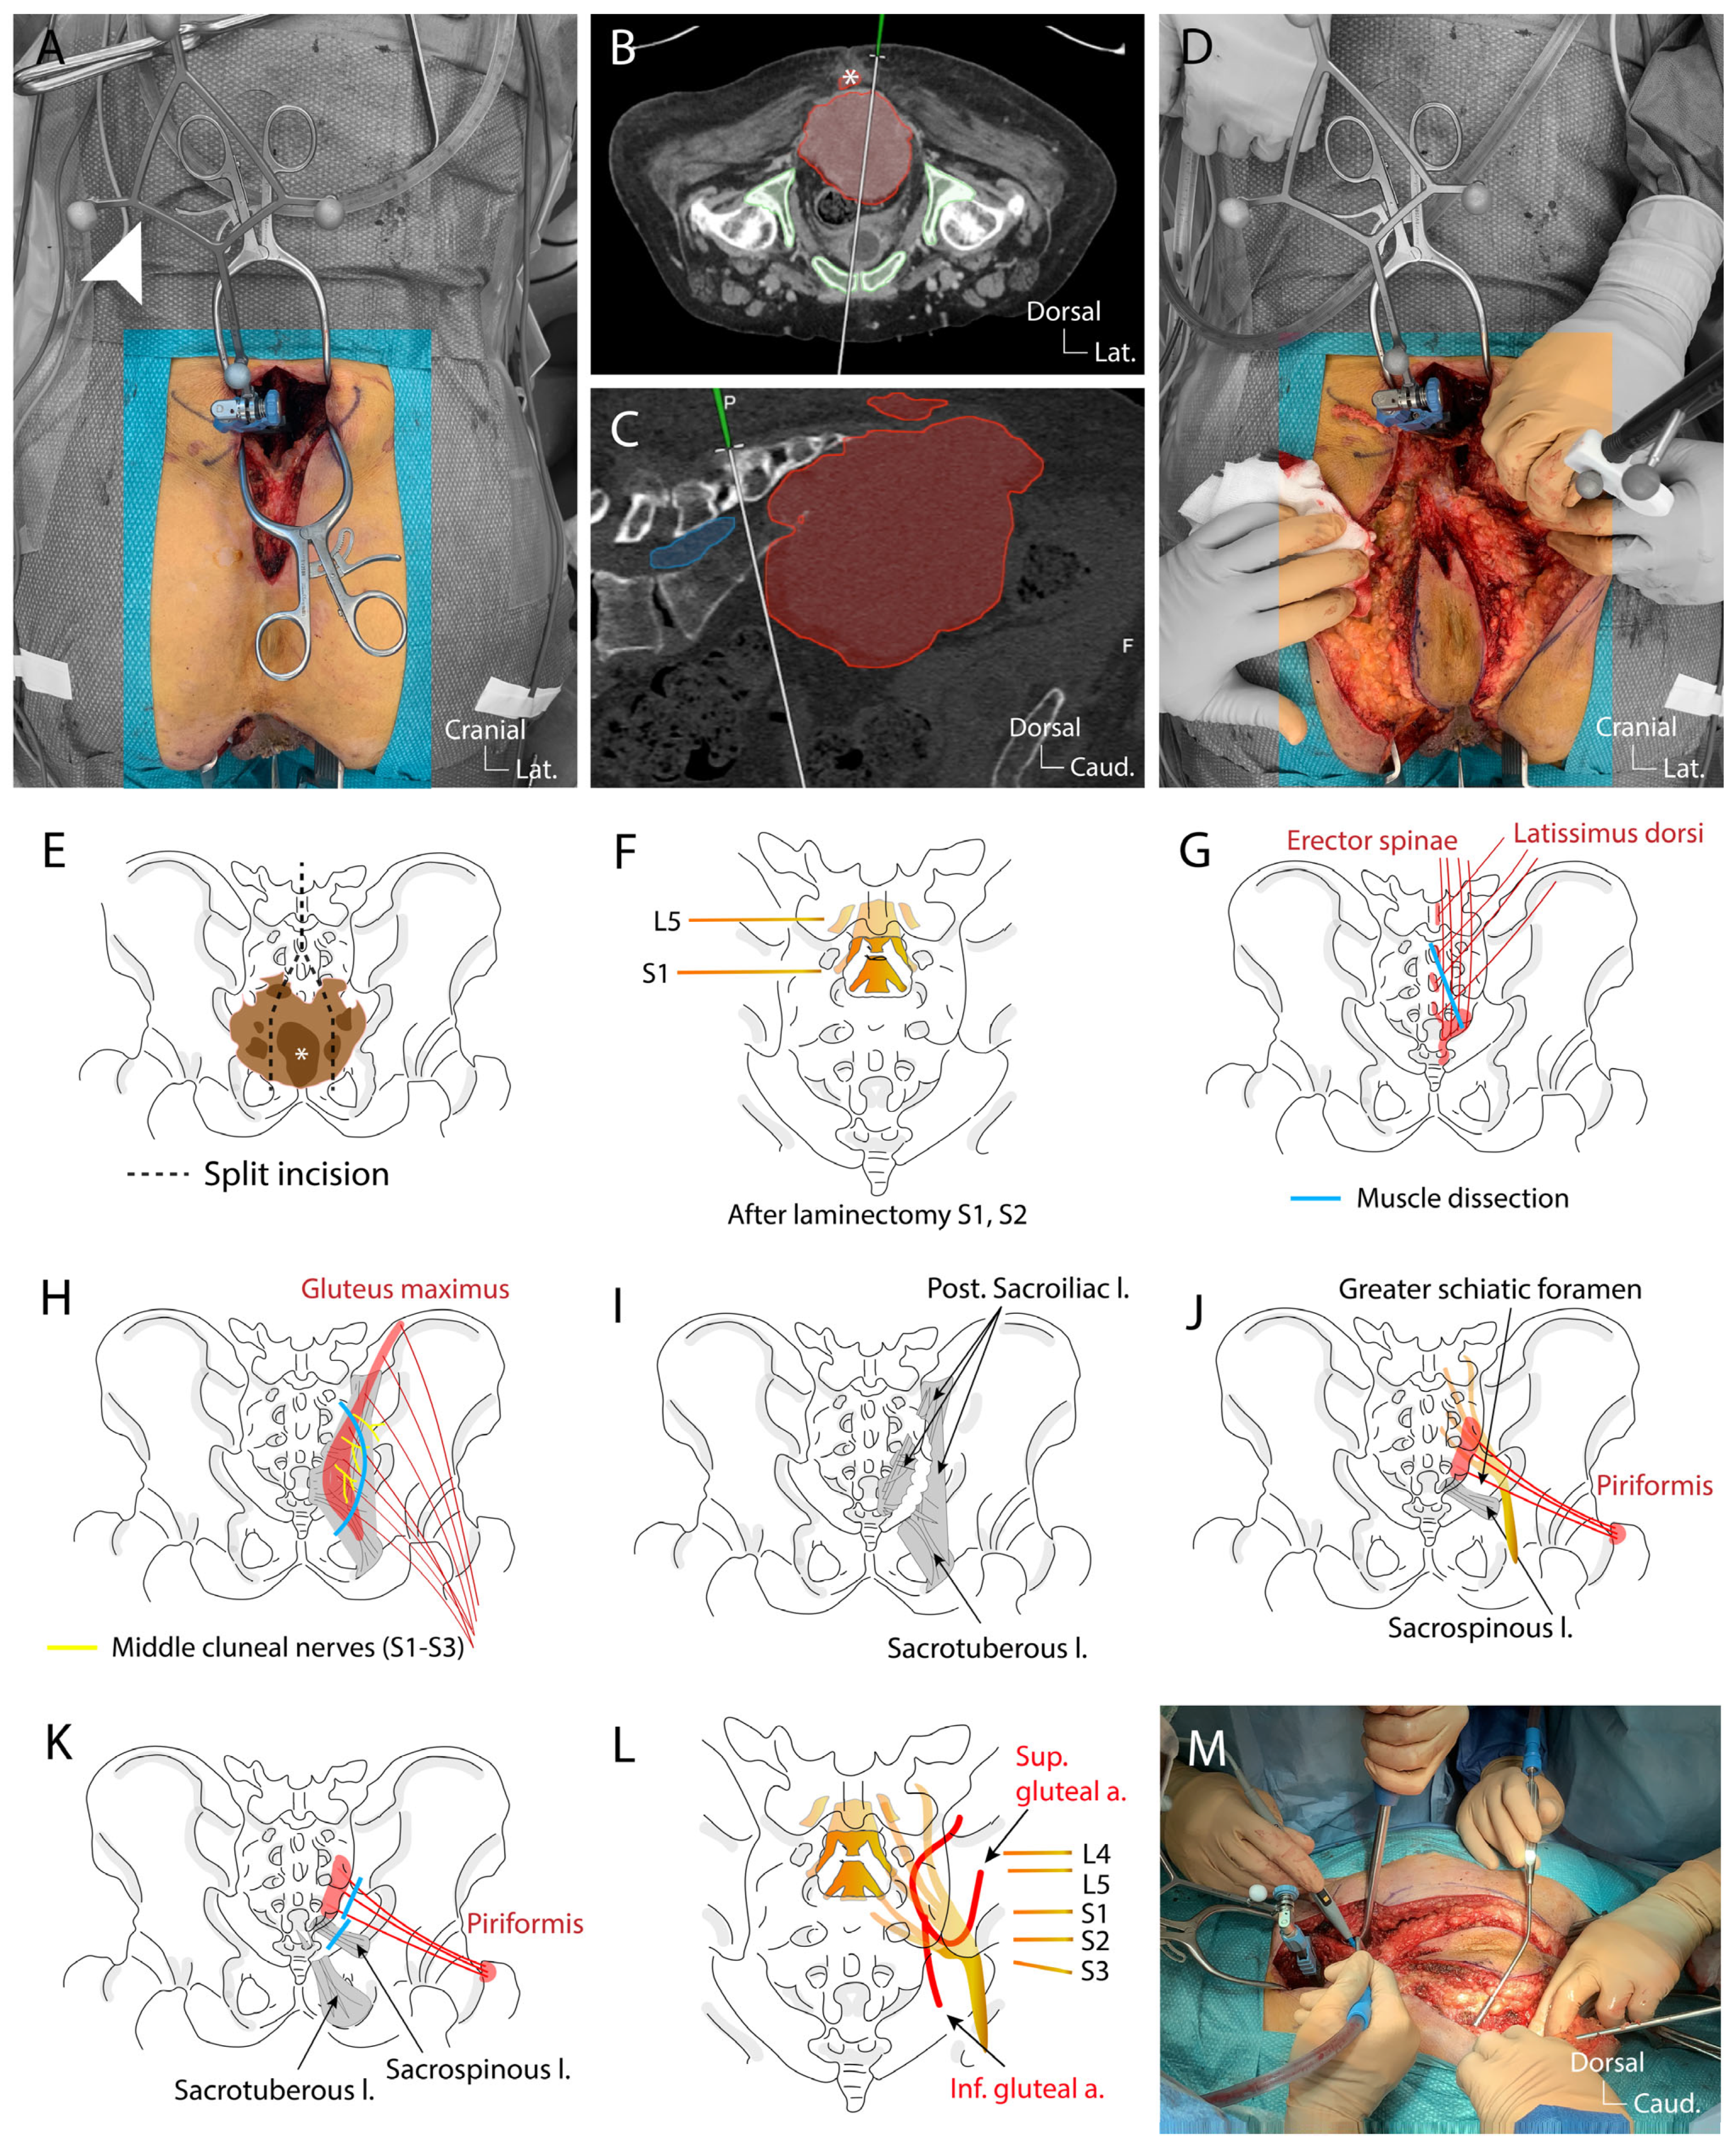

4.3. Surgical Technique